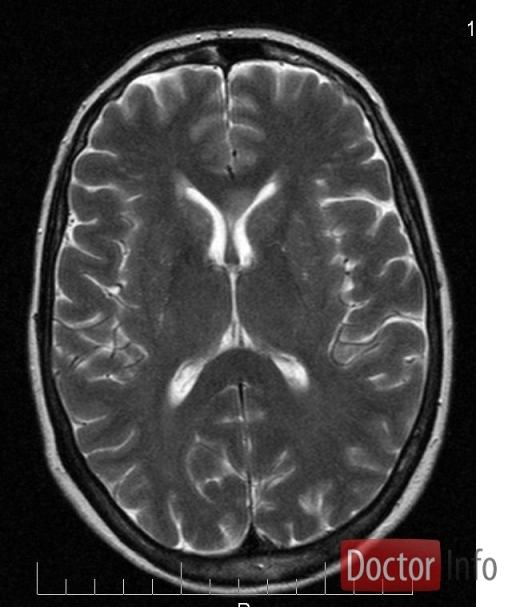

Гипертрофический узловатый глиоз

Генетическое заболевание, при котором образуются доброкачественные опухоли во многих внутренних органах. Причиной заболевания является мутация генов TSC1 и TSC2 . В основе заболевания лежит нарушение тормозного влияния этих генов на избыточное деление клеток.